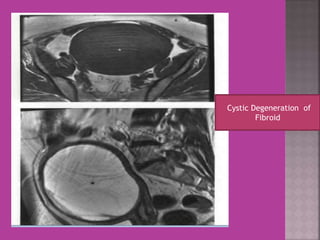

Degeneration Of Fibroid

Cystic Degeneration of

Fibroid